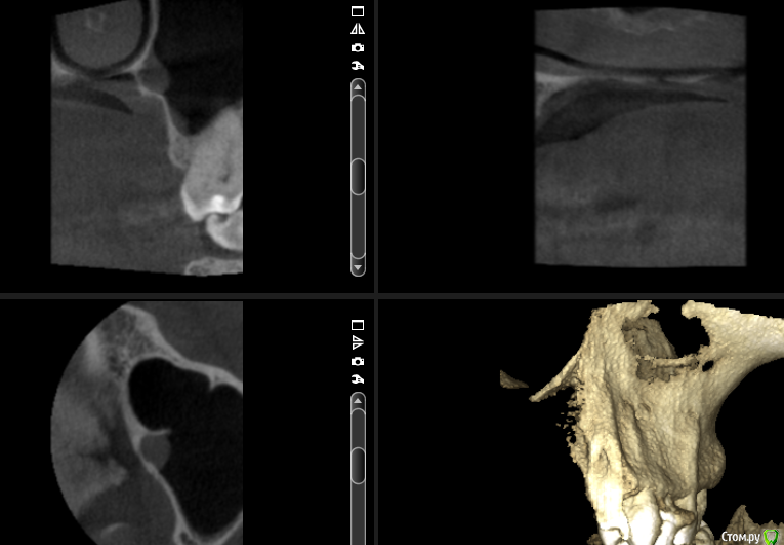

___49___ Опубликовано 19 сентября, 2016 Поделиться Опубликовано 19 сентября, 2016 (изменено) Уважаемые коллеги прошу высказать свое видение предоставленных срезов КТ ...Основной диагноз : Нейропатия второй ветви левого тройничного нерва.Из анамнеза: Пациентка отмечает появление болей (усиливающиеся при движениях левым глазом) в супро, -инфроорбитальной области после лечения 26 го зуба 3 года назад. Неэффиктивность НПВС. Мне не нравится область твердого неба по ходу одноименного нерва : увеличенный свод с диффицитом костной ткани с участками полного ее отсутствия , незначительное утолщение слизистой в верхнечелюстной пазухи и полости носа напротив выше обозначенного участка . . мысли идут в сторону деструктивных изменений связанных с пат.изменениями нервной ткани второй ветви тройничного нерва . . поделитесь своими мыслями .... Изменено 19 сентября, 2016 пользователем ___49___ 2 Ссылка на комментарий